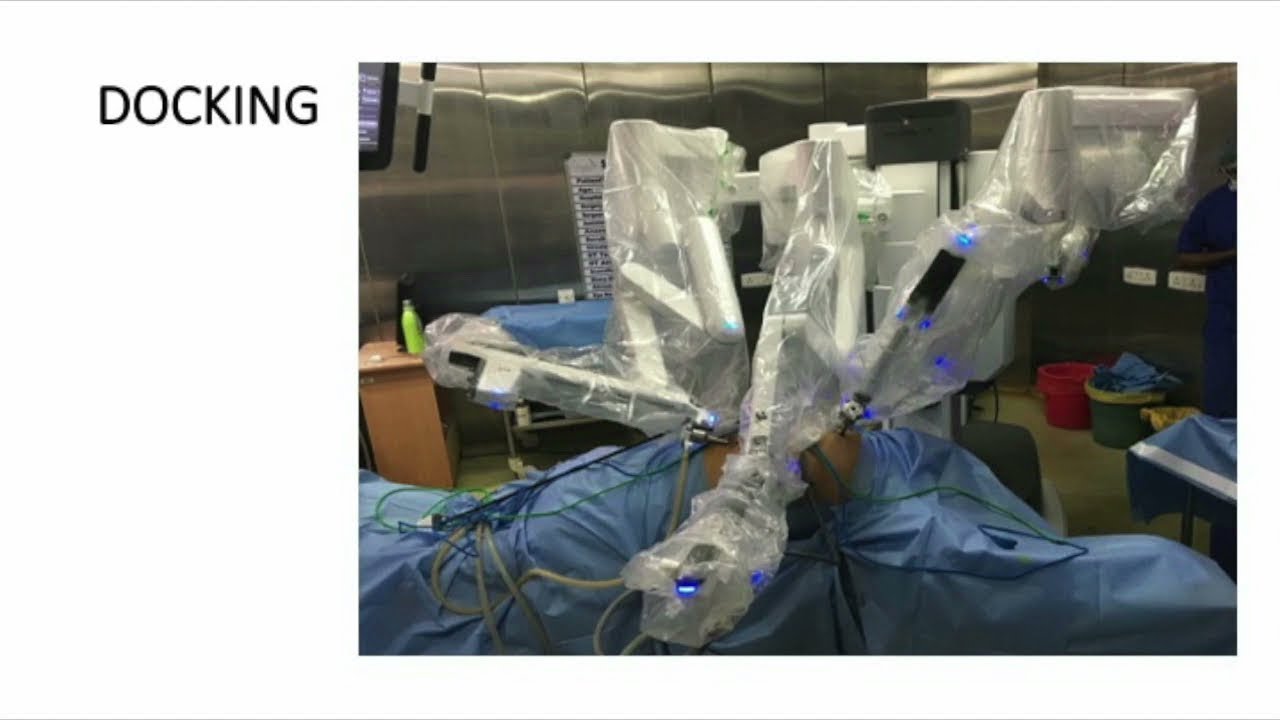

Robotic Total Pelvic Exenteration for Advanced Rectal Cancer

Robotic Total Pelvic Exenteration for Locally Advanced Rectal Cancer

Oncology, Robotics ';